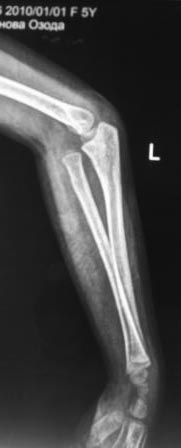

Обратилась девочка 2010г.р., 8 месяцев назад в результате падения на руку получила травму, гипсовая повязка , которую сняли через неделя и дальше не лечилась, со слов матери постепенно нарастает деформация.

Объективно отмечается волярное выбухание головки лучевой кости, и гиперэкстензия в локтевом суставе, функция почти не нарушена, супинация и пронация сохранены. Какой-то чувство, что возможно была разгибательный переломо-вывих Монтеджа. Фото руки и Р-снимки представляются.

В плане корригируюшая остетотомия на уровне с-в/з локтевой кости с восстановлением дуги локтевой кости ( сначала измерить другую локтевую кость), фиксация - или пластина или и/м штифт., вправление вывиха головки луча, восстановление кольцевидной связки из местных тканей, временная фиксация спицей к локтевой кости.-это пока предварительно то, что пришла на ум сейчас!